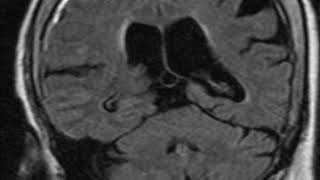

Subarachnoid Hemorrhage Mri Online

29. Intracranial Hypotension Sagging, Subdural...

Mri Brain